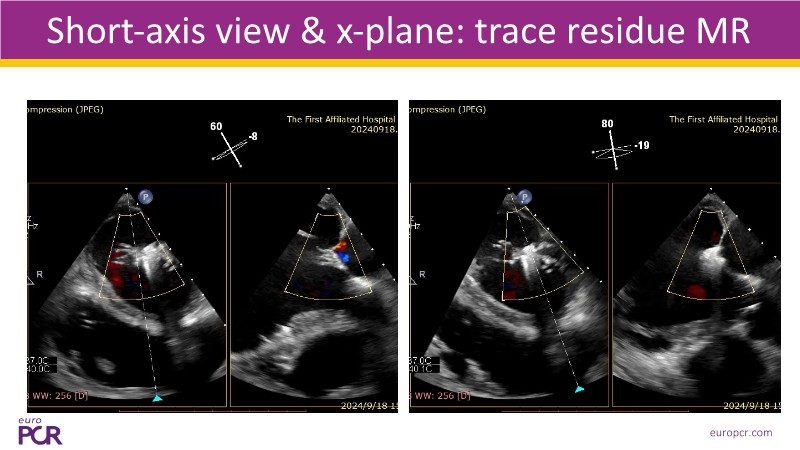

- To discover tips and techniques for mitral TEER in patients with challenging anatomy and difficult imaging